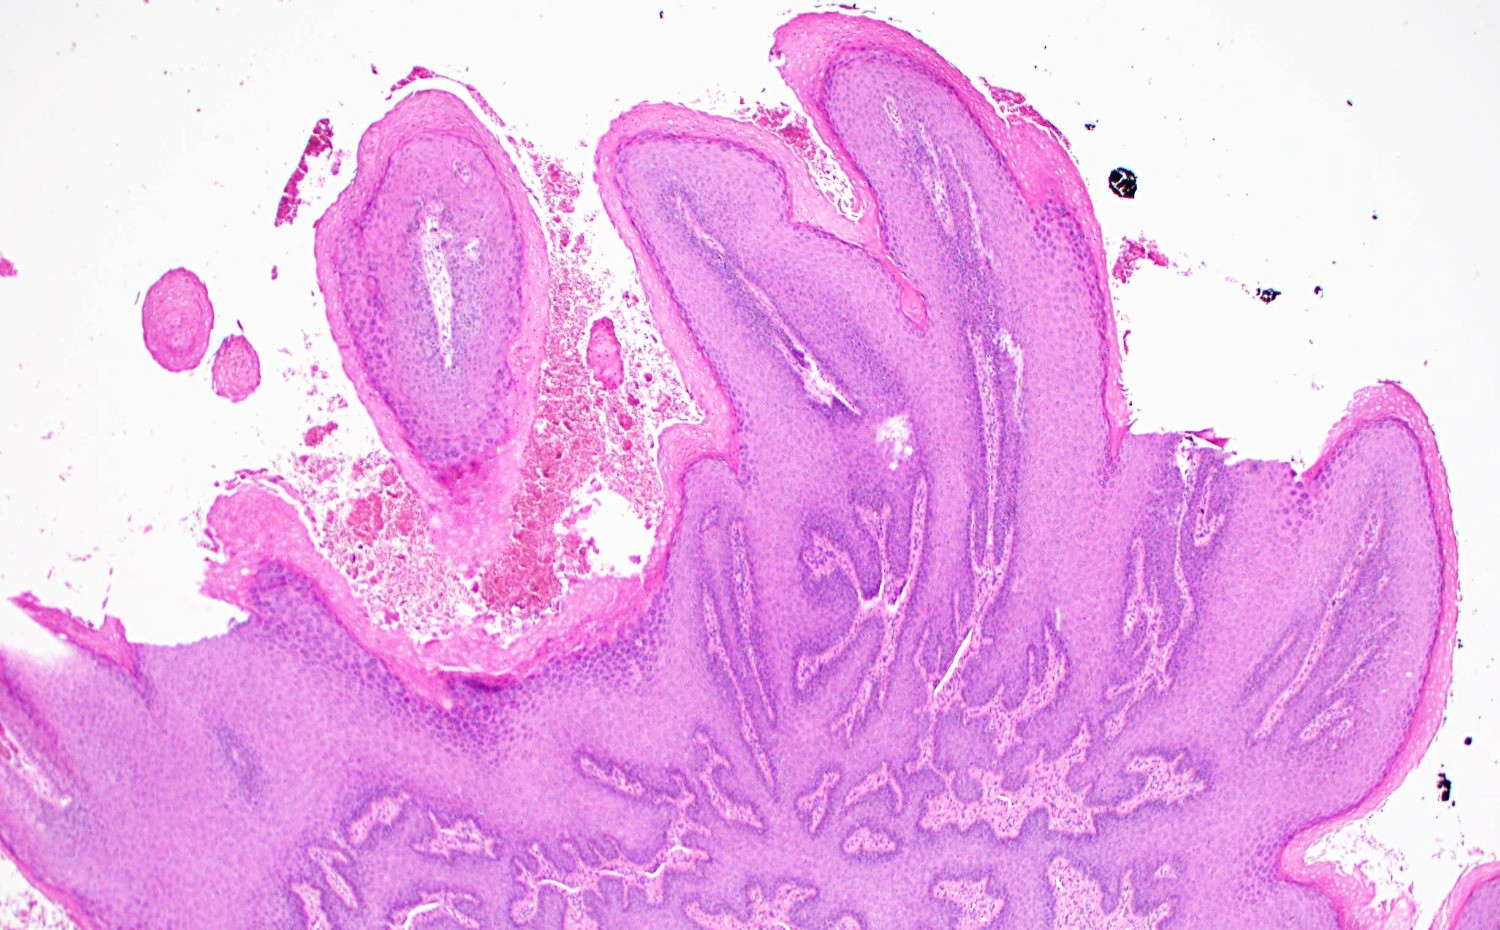

Симптомы кондилом могут варьироваться, и визуальное представление этого заболевания может быть различным. Некоторые кондиломы выглядят как небольшие бугорки или бородавки, в то время как другие могут иметь форму плоских пятен или цветных наростов.